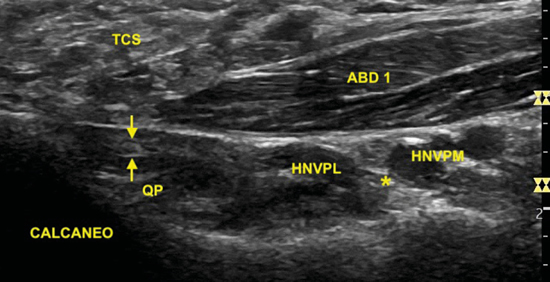

Situamos la sonda tomando como referencia la línea entre el centro del calcáneo y el vértice del maléolo tibial (Figura 15). La ecografía muestra cómo la rama de Baxter se encuentra en el espacio comprendido entre la fascia profunda del músculo abductor del primer dedo y el músculo cuadrado plantar, en la cara próxima al calcáneo5. Debido a su pequeño tamaño, entre uno y dos milímetros11, el examen ecográfico de este nervio monofascicular en el espacio entre el músculo abductor del primer dedo y el músculo cuadrado plantar es posible, aunque se hace complicado5,12 (Figura 16).

Figura 16. Ecografía de la rama de Baxter (flechas) bajo la fascia del músculo abductor del primer dedo (ABD 1) próximo a su inserción en el calcáneo y sobre el músculo cuadrado plantar (QP). Se sitúa posterior al haz neurovascular plantar lateral (HNVPL) que se encuentra separado del haz neurovascular plantar medial (HNVPM) mediante el septo de interfascicular o de Heimkes (*). TCS: tejido graso subcutáneo.